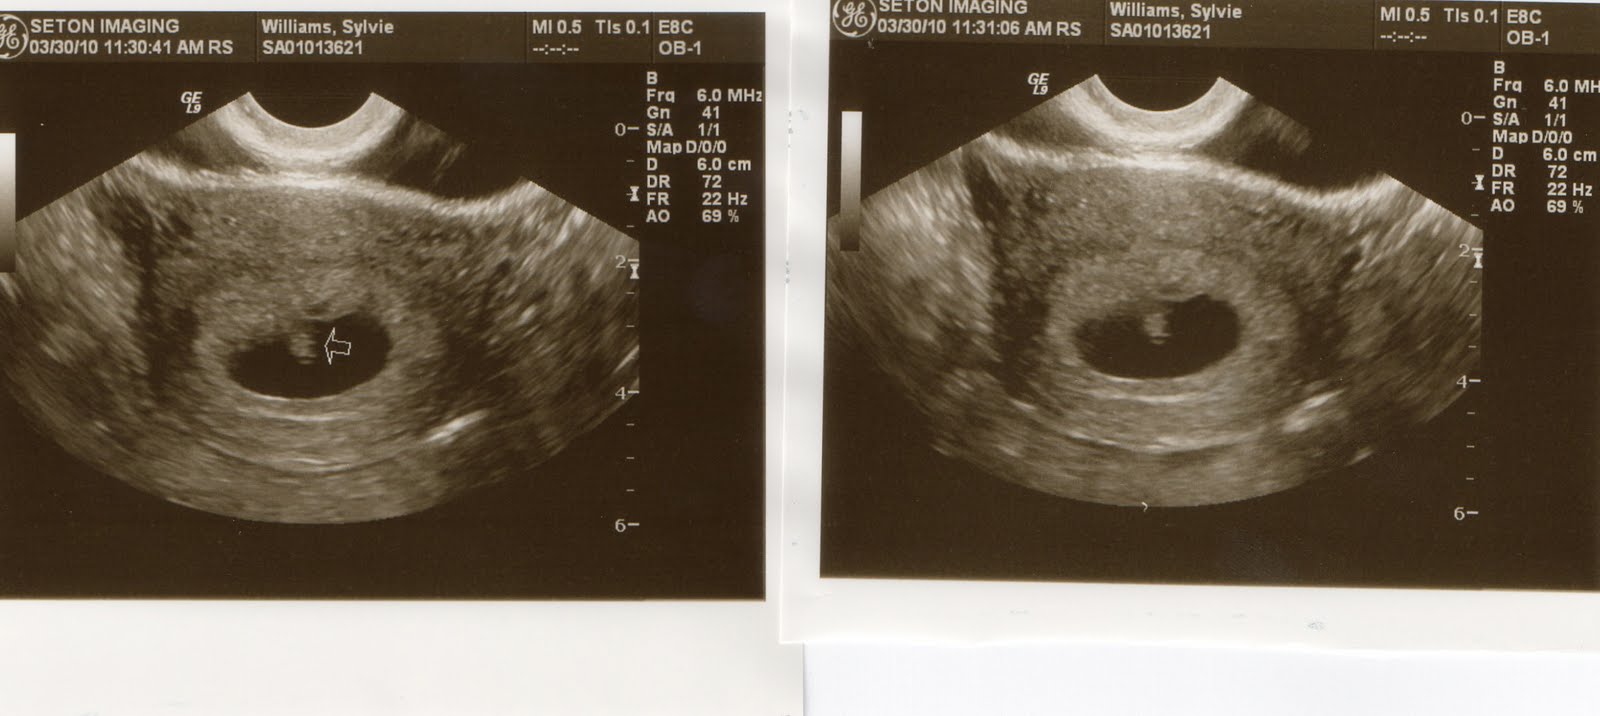

On Friday, a urine test at the OB-GYN's proved the same thing. She sent me for bloodwork the next week and we have our first ultrasound on March 30th.